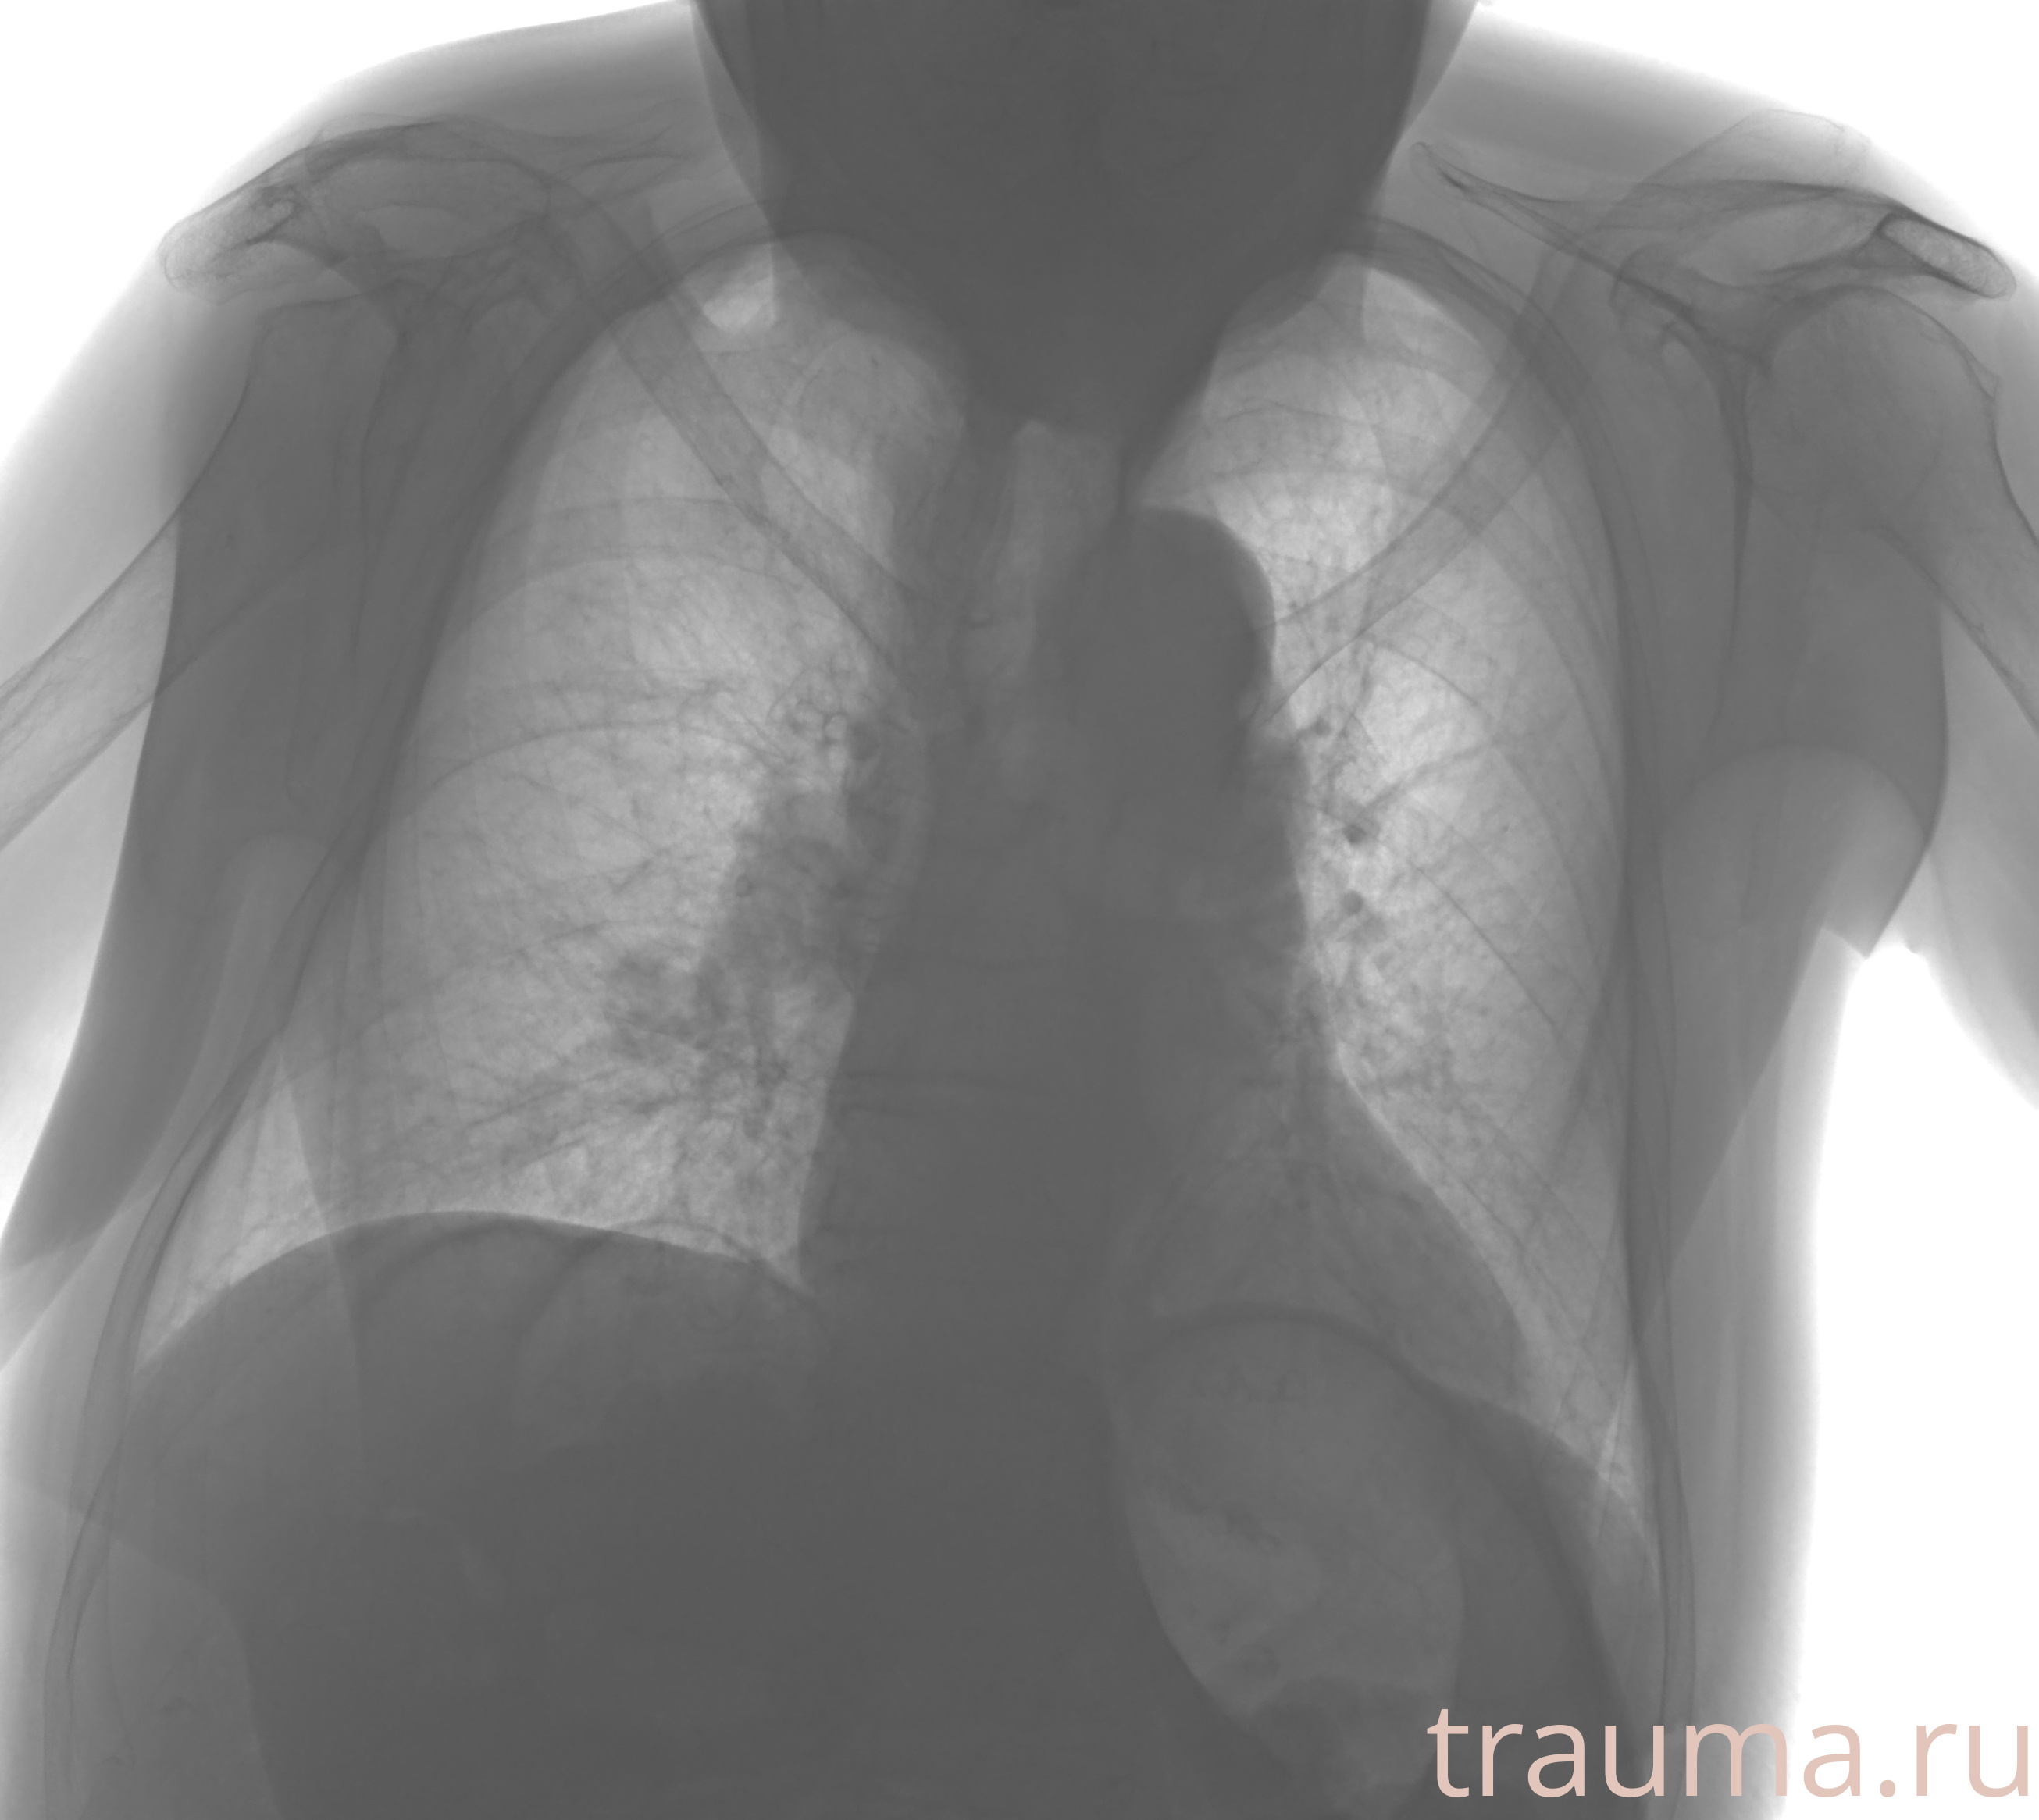

Рентгенограммы

Рентген на дому: по вашему адресу приезжает врач-рентгенолог, травматолог-ортопед с мобильным рентгеновским аппаратом, проводит диагностику травмы или заболевания, делает необходимые рентгенограммы, дает рекомендации по дальнейшему лечению. Получить качественные снимки в домашних условиях возможно благодаря уникальной методике, разработанной МосРентген Центром для института  Склифосовского

Яркость: 1   Контраст: 1   Инвертировать: 0 Увеличение: 1

Перетаскивайте мышь вверх/вниз для контраста, влево/право для яркости. Прокрутка колесом изменяет масштаб. Нажмите Сбросить для возврата к исходному изображению. При увеличении держите мышь в той области, которую хотите рассмотреть.